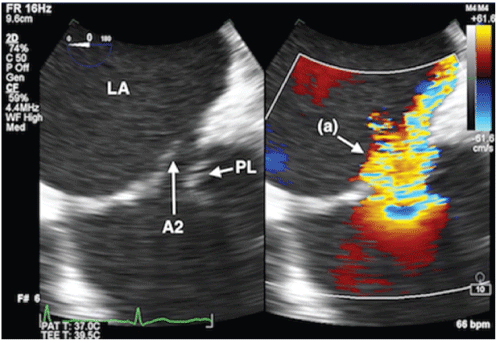

图6:新的第二夹子(a)的正面三维视图被推进到第一个分离夹子(b)的侧面,也可以看到。第二段剪辑仍然连接在这个图像中的部署设备(c)上。